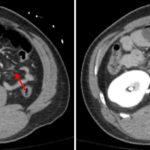

- Complex laceration involving the superior pancreatic body with surrounding parenchymal contusion

- Adjacent hemorrhage with a small contrast density focus which enlarges on delayed phase images

- Moderate volume of hemoperitoneum, primarily in the lesser sac, perihepatic space, and subhepatic space

- Scattered interloop fluid in the jejunal mesentery

Complex laceration involving the superior pancreatic body with surrounding parenchymal contusion and adjacent hematoma in the anterior pararenal space and lesser sac with small focus of active hemorrhage. Given extensive involvement of the pancreatic body, a pancreatic duct injury is not excluded.

Scattered interloop fluid in the jejunal mesentery raises concern for mesenteric injury.